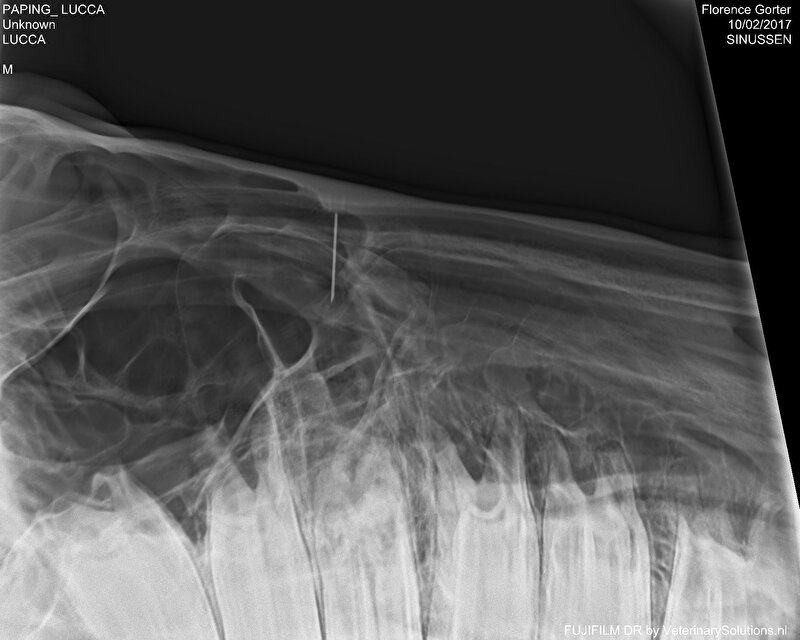

Ergens in september werd de bult groter, dus weer Echo gemaakt, röntgenfoto's van gemaakt, vocht afgenomen. Bleek pus te zijn, maar stond nergens mee in verbinding.

Open gemaakt (boven en onder de bult, dus als een soort tunnel), uitgeruimd, spoelen met fysiologisch zout enz.. Uiteindelijk te snel dichtgegroeid, dus nog een keer open gemaakt, maar op een iets andere manier. Het laatste beetje ging erg langzaam, maar nu is het zo goed als dicht.

Lijkt er wel op. Maar hij heeft geen bult de tunnel is open maar zeer klein.. Op de foto zie je de opgedroogde pus.